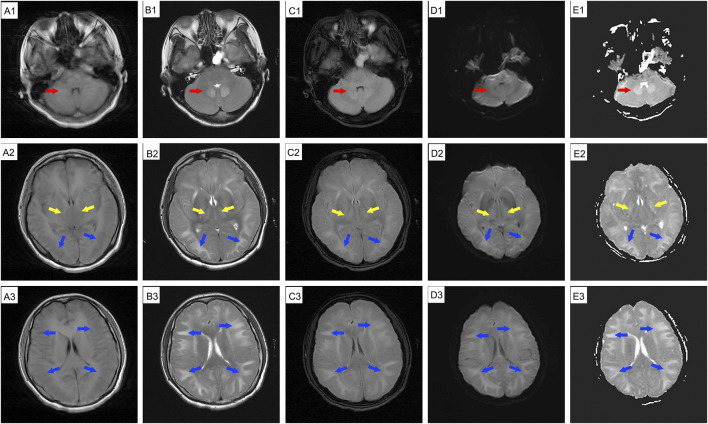

背景:1,2-二氯乙烷是一种常用的工业溶剂。急性或亚急性职业性接触可引起中毒性脑病;然而,脑成像的长期变化并不经常被记录下来。病例介绍:一名39岁女性在涂胶9天后出现头晕和健忘。休息7天后,她的症状明显好转。然而,恢复工作3天后,她返回时出现头晕、头痛和焦虑。脑磁共振成像(MRI)显示小脑齿状核、基底节区和双侧脑白质广泛水肿和弥漫性异常信号。给予丹参酚酸注射液、异甘草酸镁及神经营养治疗。入院两周后,除轻度行走不协调外,患者症状明显改善。异常MRI信号的范围与先前的发现一致。她第二天就出院了。3天后头痛加重。计算机断层扫描显示弥漫性脑水肿。尽管用甘露醇治疗,她的头痛迅速恶化,并伴有恶心、呕吐、高血压、心动过缓和呼吸困难,最终导致昏迷。后续MRI显示与前次扫描相似,只是表观扩散系数(ADC)序列由低信号变为高信号。核磁共振检查后不久,她出现呼吸骤停。不幸的是,由于严重的脑损伤和感染,她在初次入院32天后死亡。结论:职业性暴露于1,2-二氯乙烷可导致中毒性脑病,表现为弥漫性进行性脑水肿。该病例表明,脑成像结果可能并不总是与患者的临床状况相关,因此仔细监测是必不可少的。

Case presentation: A 39-year-old woman developed dizziness and forgetfulness 9 days after performing glue coating. Her symptoms improved significantly after a 7-day break from work. However, after resuming work for 3 days, she returned with dizziness, headache, and anxiety. Brain magnetic resonance imaging (MRI) showed extensive edema and diffuse abnormal signal intensities in the cerebellar dentate nucleus, basal ganglia, and bilateral cerebral white matter. She was treated with salvianolate injection, magnesium isoglycyrrhizinate, and neurotrophic therapy. Two weeks after admission, her symptoms improved significantly, except for mild uncoordinated walking. The range of abnormal MRI signals remained consistent with previous findings. She was discharged the following day. She experienced worsened headache 3 days later. Computed tomography revealed diffuse cerebral edema. Despite treatment with mannitol, her headache rapidly worsened and was accompanied by nausea, vomiting, hypertension, bradycardia, and dyspnea, ultimately leading to unconsciousness. Follow-up MRI showed findings similar to the previous scan, except that the apparent diffusion coefficient (ADC) sequence had changed from hypointense to hyperintense. Shortly after the MRI examination, she experienced respiratory arrest. Unfortunately, she died 32 days after her initial admission due to severe cerebral injury and infection.

Conclusion: Occupational exposure to 1,2-dichloroethane can lead to toxic encephalopathy, presenting as diffuse progressive cerebral edema. This case shows that brain imaging findings may not always correlate with the patient's clinical condition, so careful monitoring is essential.